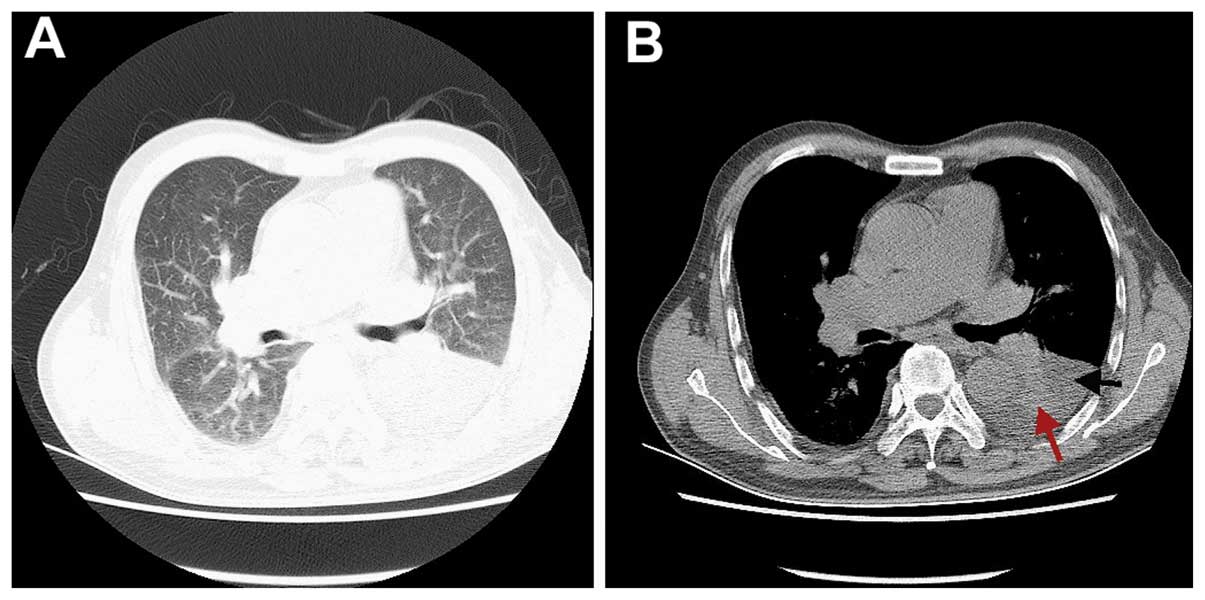

A 70-year-old male patient presented at The First Affiliated Hospital of Wenzhou Medical University (Wenzhou, China) with a 1-week history of cough and exertional dyspnea with no fever, chest pain, purulent sputum and hemoptysis. The patient was a smoker with >20 pack-years, but his medical, social and family history were otherwise unremarkable. On physical examination, the patient appeared pale, with decreased breath sounds and dullness on percussion over the left posterior thorax. The laboratory findings were as follows: White blood cell count, 3.9×109/l (50.9% neutrophils, 32.7% lymphocytes, and 13.5% monocytes, normal basophils and eosinophils); erythrocyte count, 2.7×1012/l; hemoglobin, 81 g/l; platelet count, 180×109/l; total protein, 85.5 g/l; albumin, 31.8 g/l; globulin, 53.7 g/l; serum calcium, 3.6 mmol/l [normal limit (NL): 2.1–2.6 mmol/l]; serum creatinine, 180 µmol/l (NL: 44–97 µmol/l); urea nitrogen, 8.7 mol/l; C-reactive protein, 30.5 mg/l; lactate dehydrogenase (LDH), 364.0 µ/l; β2-microglobulin, 21.1 µg/ml (NL: 0.9–2.7 µg/ml); serum κ light chain, 3.4 g/l (NL: 6.3–13.5 g/l); serum λ light chain, 28.3 g/l (NL: 3.1–7.2 g/l); serum IgA, 24.3 g/l; IgM, 153.00 mg/l; IgG, 4.4 g/l; and IgM, 0.43 g/l; the IgE and IgD levels were normal. Carcinoembryonic antigen (CEA), carbohydrate antigen 19-9 and brain natriuretic peptide levels were within normal limits, and the T-SPOT® tuberculosis test was negative. Computed tomography (CT) revealed left pleural effusion and atelectasis of the lower lobe of the left lung (Fig. 1). Fiberoptic bronchoscopy revealed no endobronchial lesions. The patient underwent thoracentesis and the pleural fluid was highly cellular, with a nucleated cell count of 1.7×109/l (42% mononuclear cells), and contained total protein at 46.1 g/l, LDH at 193.0 U/l, adenosine deaminase at 20.0 U/l and CEA at 1.5 µg/l; thus, the effusion was considered as exudative according to the Light criteria (2). Malignant cells were not found in the pleural fluid. Immune fixation electrophoresis of the blood revealed IgA-λ-type monoclonal immunoglobulin. The patient underwent bone marrow aspiration biopsy twice. The first bone marrow biopsy showed no significant abnormalities (Fig. 3A), while the second revealed a mildly hypercellular marrow with 13% plasma cells (Fig. 3B). Semi-rigid thoracoscopy was performed, which revealed a solitary pleural nodule sized ~1×0.8 cm on the parietal pleura (Fig. 4). Histopathological evaluation of the biopsied nodule revealed sheets of neoplastic plasma cells, which were positive for CD38 and multiple myeloma oncogene 1 (MUM1), with λ light chain restriction and a Ki-67 index of 50% (Fig. 5). The patient was diagnosed with IgA-λ-type MM with pleural involvement, based on the clinical manifestations, laboratory examinations, radiographic findings and the results of bone marrow and pleural biopsies. The patient received chemotherapy with bortezomib, epiadriamycin and dexamethasone; however, he deteriorated rapidly after one cycle of chemotherapy and succumbed to the disease 8 weeks after the initial presentation.

Figure 1.

Computed tomography scans of the chest. (A) Lung window and (B) mediastinal window showing left pleural effusion (black arrow) and compressive atelectasis of the lung (red arrow).